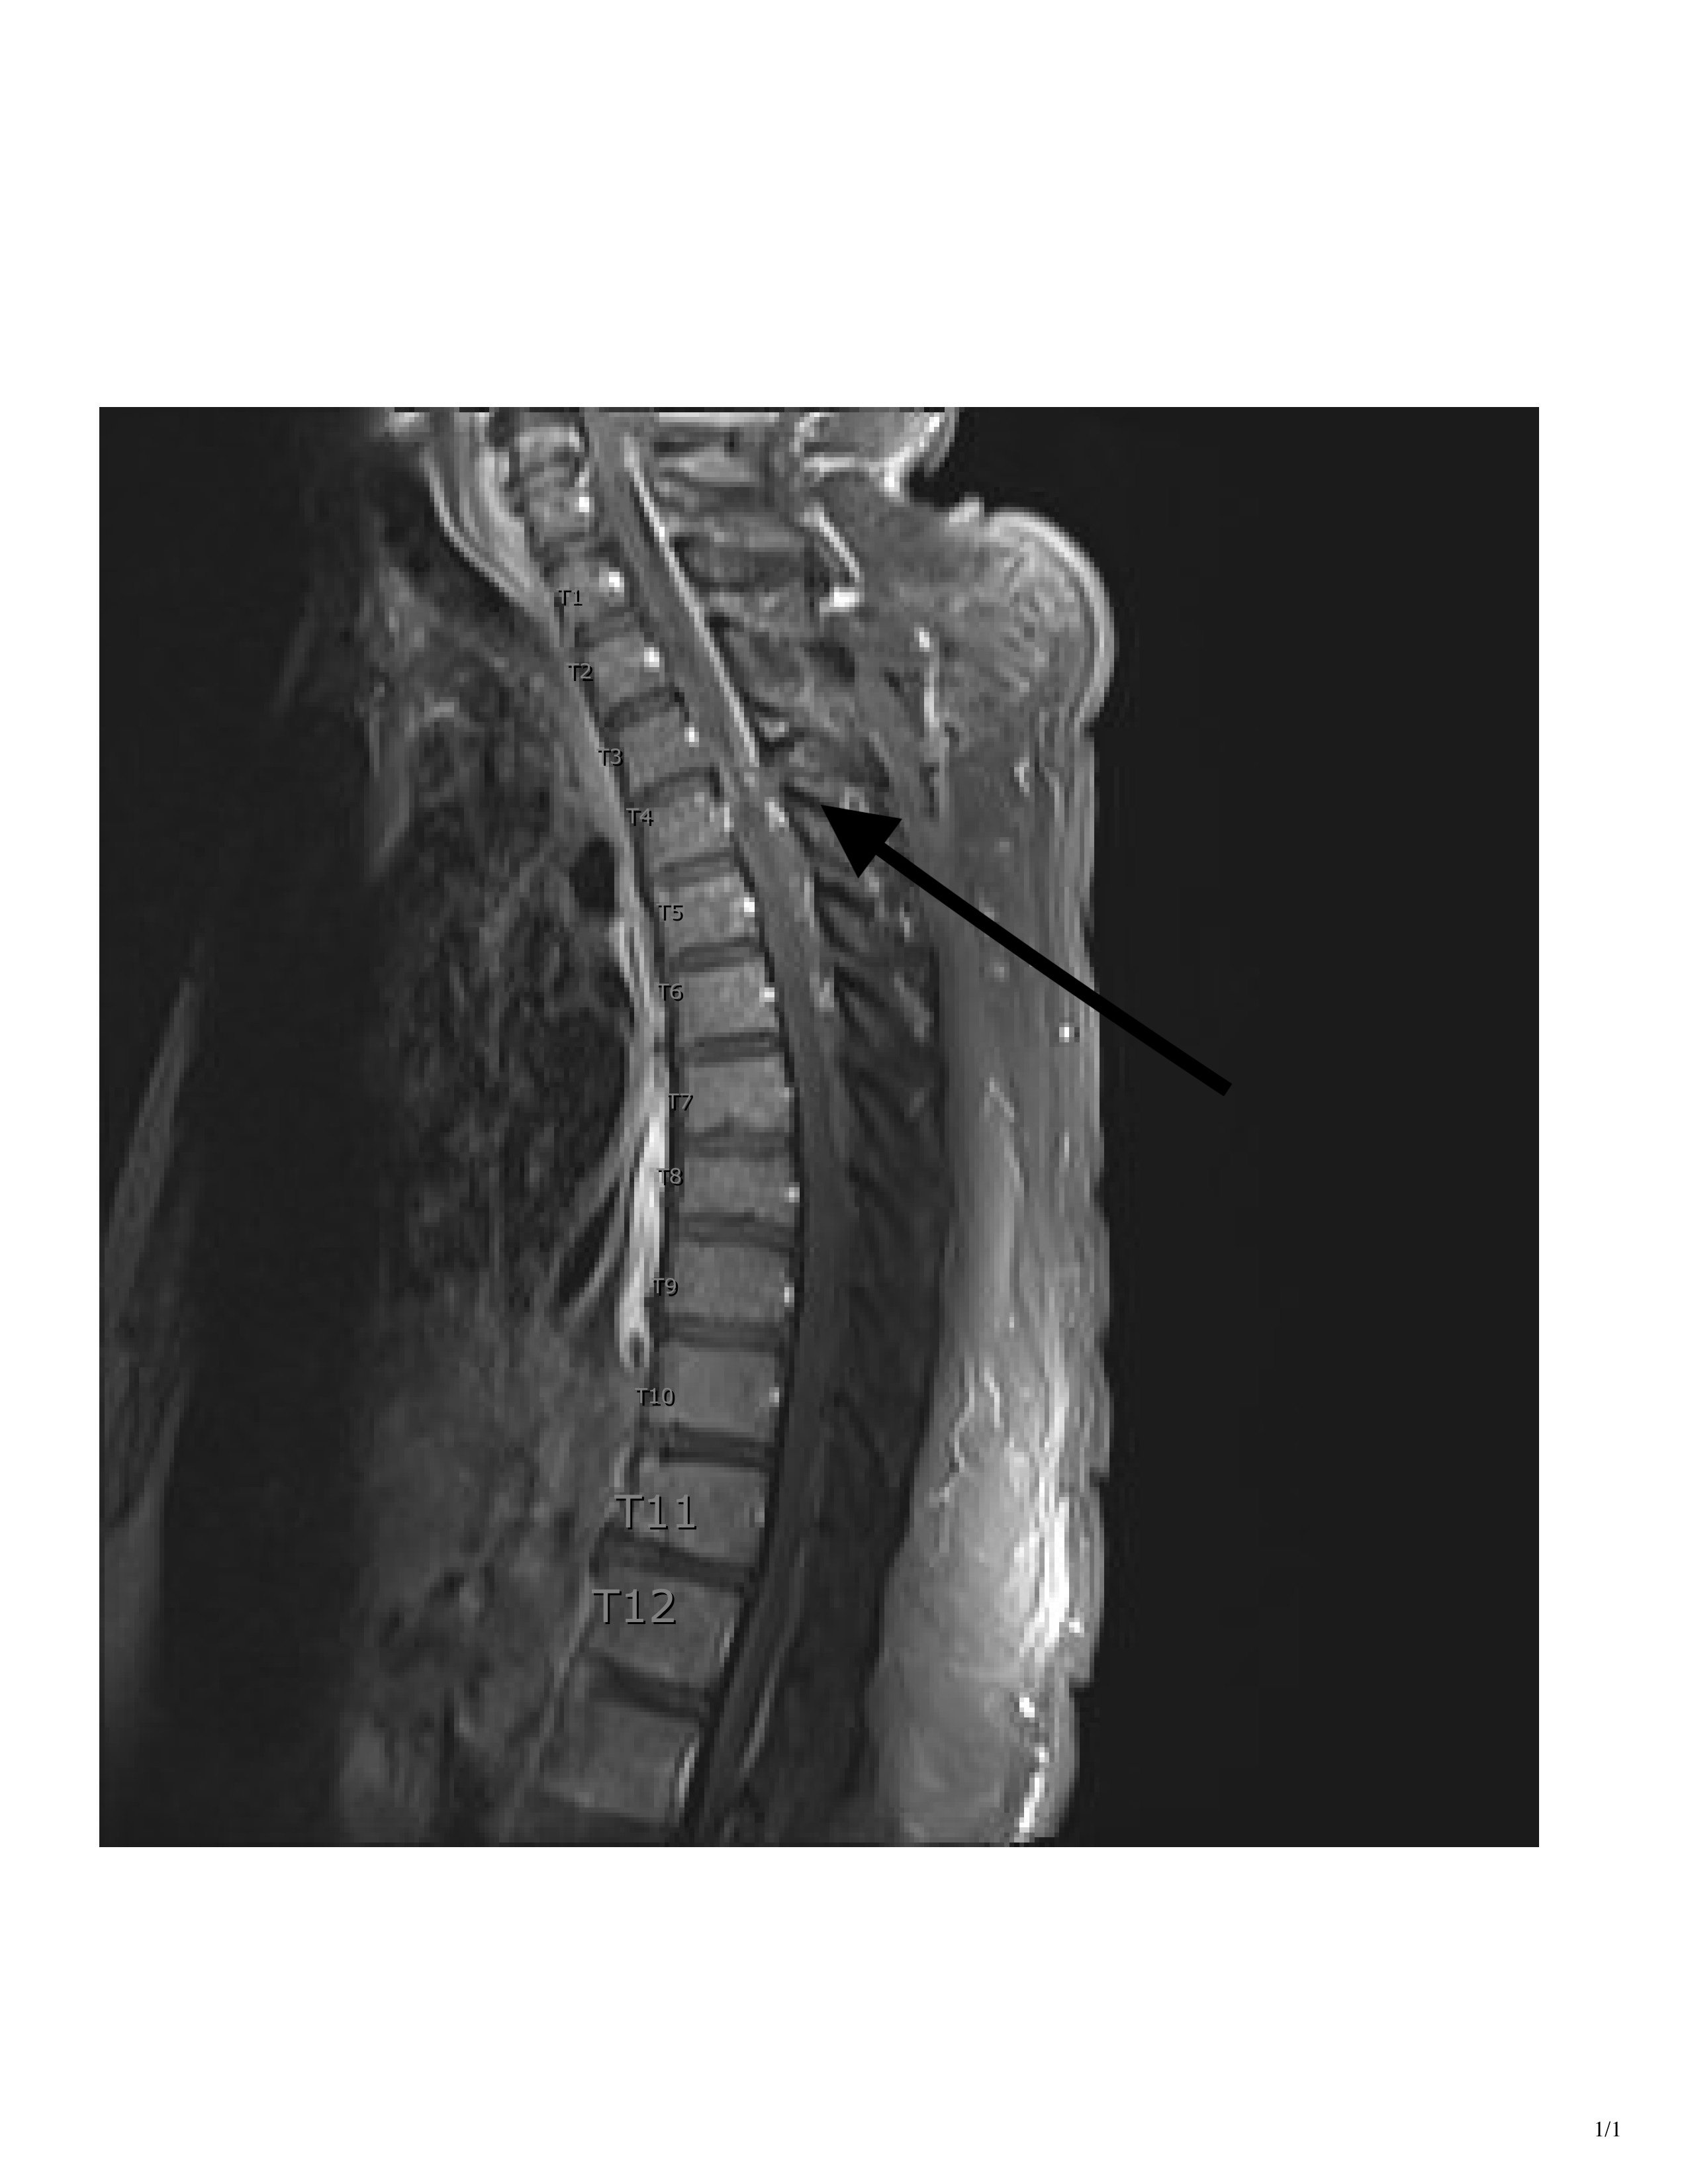

CT imaging showed a T3 spinous process fracture raising concern for intracanal blood products and possible cord injury. MRI later that night confirmed cord contusion with possible injury to the right hemi cord, and dorsal epidural hematoma extending from T2 to T10.

Although this patient’s penetrating wound entered on the left paraspinal region and fractured through the spinous process on the left, it injured the cord on the right side. Given that only one side of the patient’s cord was injured, the deficits depended on where the different pathways were injured in relation to their areas of decussation (crossing over).

At the time of presentation, we knew the patient displayed clinical signs of Brown-Séquard, and the CT showed injury on the right side of the cord. What was unclear at the time was whether the patient had a true hemi-section of the spinal cord, leading to permanent disability, or if he was instead suffering from a transitory spinal shock due to swelling and hematoma.

An MRI obtained the next day confirmed right-sided spinal cord hemi-section, as well as associated cord contusion and epidural hematoma. Additionally, when the patient was discharged from the Shock Trauma ICU several days later, he was still exhibiting the same neurological deficits. The patient was discharged directly to a rehabilitation center, where occupational and physical therapists were expected to help him maximize his recovery and learn to live with his new deficits.